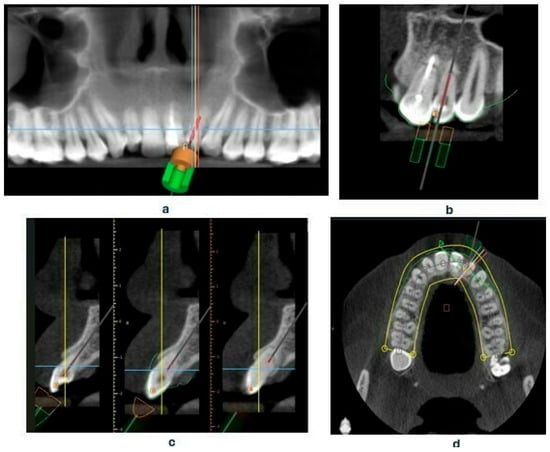

The standard tessellation language (STL) (a file format native to the stereolithography CAD software created by the 3D system) files containing the intraoral scan and the CBCT of the entire dental arch were uploaded into the Blue Sky Plan 4 software. Within this program, a template was designed that included a sleeve intended to guide the endodontic instrument, specifically the Munce Discovery Bur (CJM Engineering, Santa Barbara, CA, USA) used for locating the root canal opening.

Based on the CBCT images and the scans, a template was designed that covers the surfaces of all teeth in the arch, including the palatal and labial surfaces [17]. The template is set to plan the drill position—including the position, length—0 mm, apical diameter—1.05 mm, occlusal diameter—1.55 mm, as well as the dimensions of the software guide tube (offset—10.5 mm—meaning the distance from the tooth, height—5 mm, and guide hole diameter—1.05 mm) (Figure 4a–d). Additionally, the planned length for accessing the root canal will also be determined—18 mm.

Figure 4. Presenting the creation of an endodontic template, (a) settings of drill position in Blue Sky Plan software panoramic view, (b) coronal view, (c) sagittal view, (d) axial view.

After the design was approved, the STL file of the template project was exported from the planning software (Blue Sky Plan 4 version 4.12.3) and processed in Chitubox software version 2.0.0 (Figure 5).